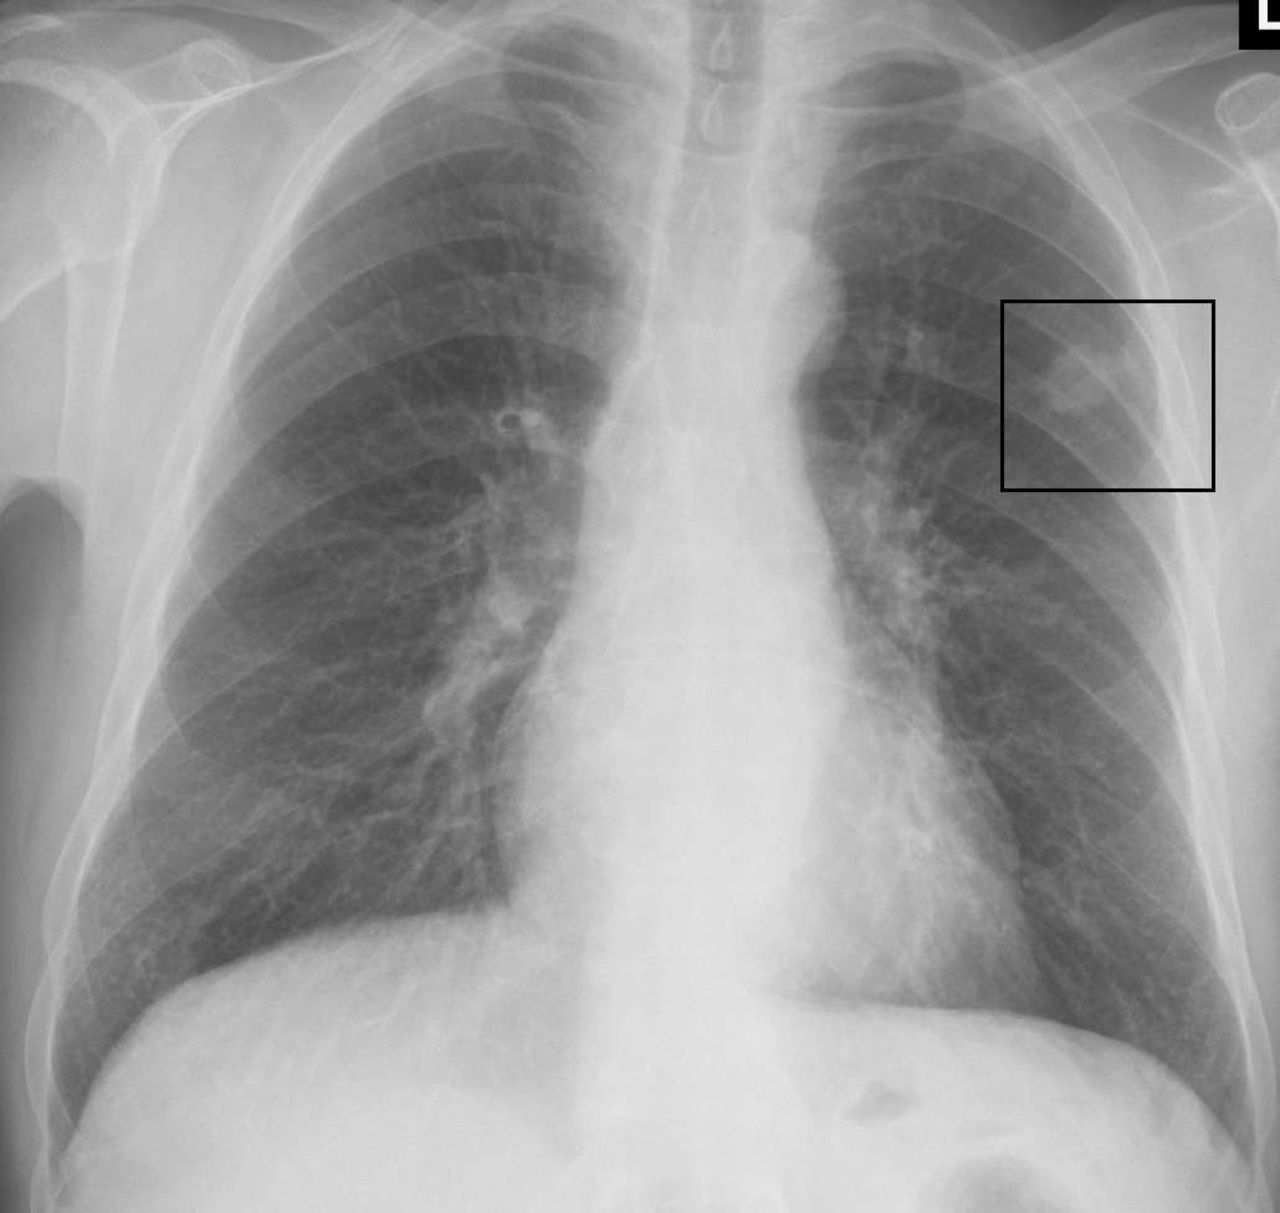

Google tar fram piller som kan upptäcka cancer Och andra sjukdomar Google tar fram piller som kan upptäcka cancer Röntgenbild som visar lungcancer Foto: Lange123 / Wikipedia Google utvecklingsavdelning Google X arbetar på att ta fram ett piller som ska kunna upptäcka cancer förestående hjärtattacker och andra sjukdomar i en människas kropp.Pillret använder sig av nanoteknik och små magnetiska nanopartiklar i pillret ska ha möjligheten att upptäcka molekyler i kroppen som tyder på att man har en viss sjukdom. Man kan sedan samla ihop nanopartiklarna via till exempel ett magnetiskt armband och analysera resultatet. Andrew Conrad, forskningschef på Google X, säger till Wired: